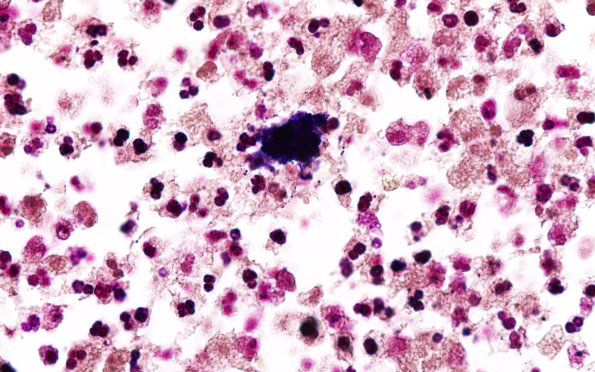

Washington University Experience | INFECTION | Bacteria | Abscess | Abscess, Subacute - Chronic | 17D2 Abscess (Case 17) N12 Gram 100X 1

The same area stained with a Gram stain showing cocci in this bacterial cloud. (Gram stain)